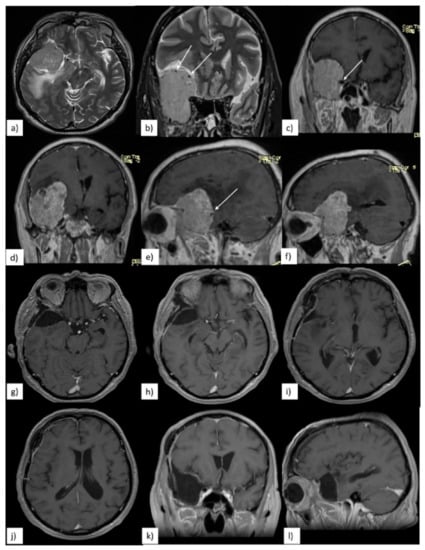

3.2. Preoperative Clinical and Radiological Data

3.3. Quality of Resection

3.4. Postoperative Clinical Evolution and Follow-up

| Immediate Postoperative Clinical Evolution | Quality of Resection and Tumoral Progression | ||||

|---|---|---|---|---|---|

| Clinical Data | n (%) | Radiological Data | n (%) | ||

| unchanged | 14 (67%) | GTR | 14 (67%) | ||

| worsened | total | 7 (33%) | |||

| visual disfunctions | 4 (19%) | STR | 7 (33%) | ||

| motor deficits | 2 (9.5%) | location of residual tumor | total | 7 | |

| aphasia | 1 (4.7%) | cavernous sinus | 4 (57%) | ||

| long term clinical follow-up | ICA/MCA | 2 (29%) | |||

| improved | 17 (81%) | sphenoidal ridge | 1 (14%) | ||

| worsened | 2 (9.5%) | site of residual tumor which required surgical reintervention | cavernous sinus | 2 (9.5%) | |

| deaths | 2 (9.5%) | ||||

| surgical reintervention | 2 (9.5%) | ||||